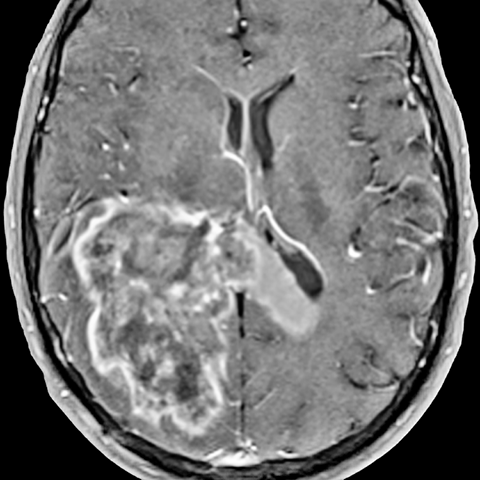

Glioblastoma Multiforme [2 of 2]